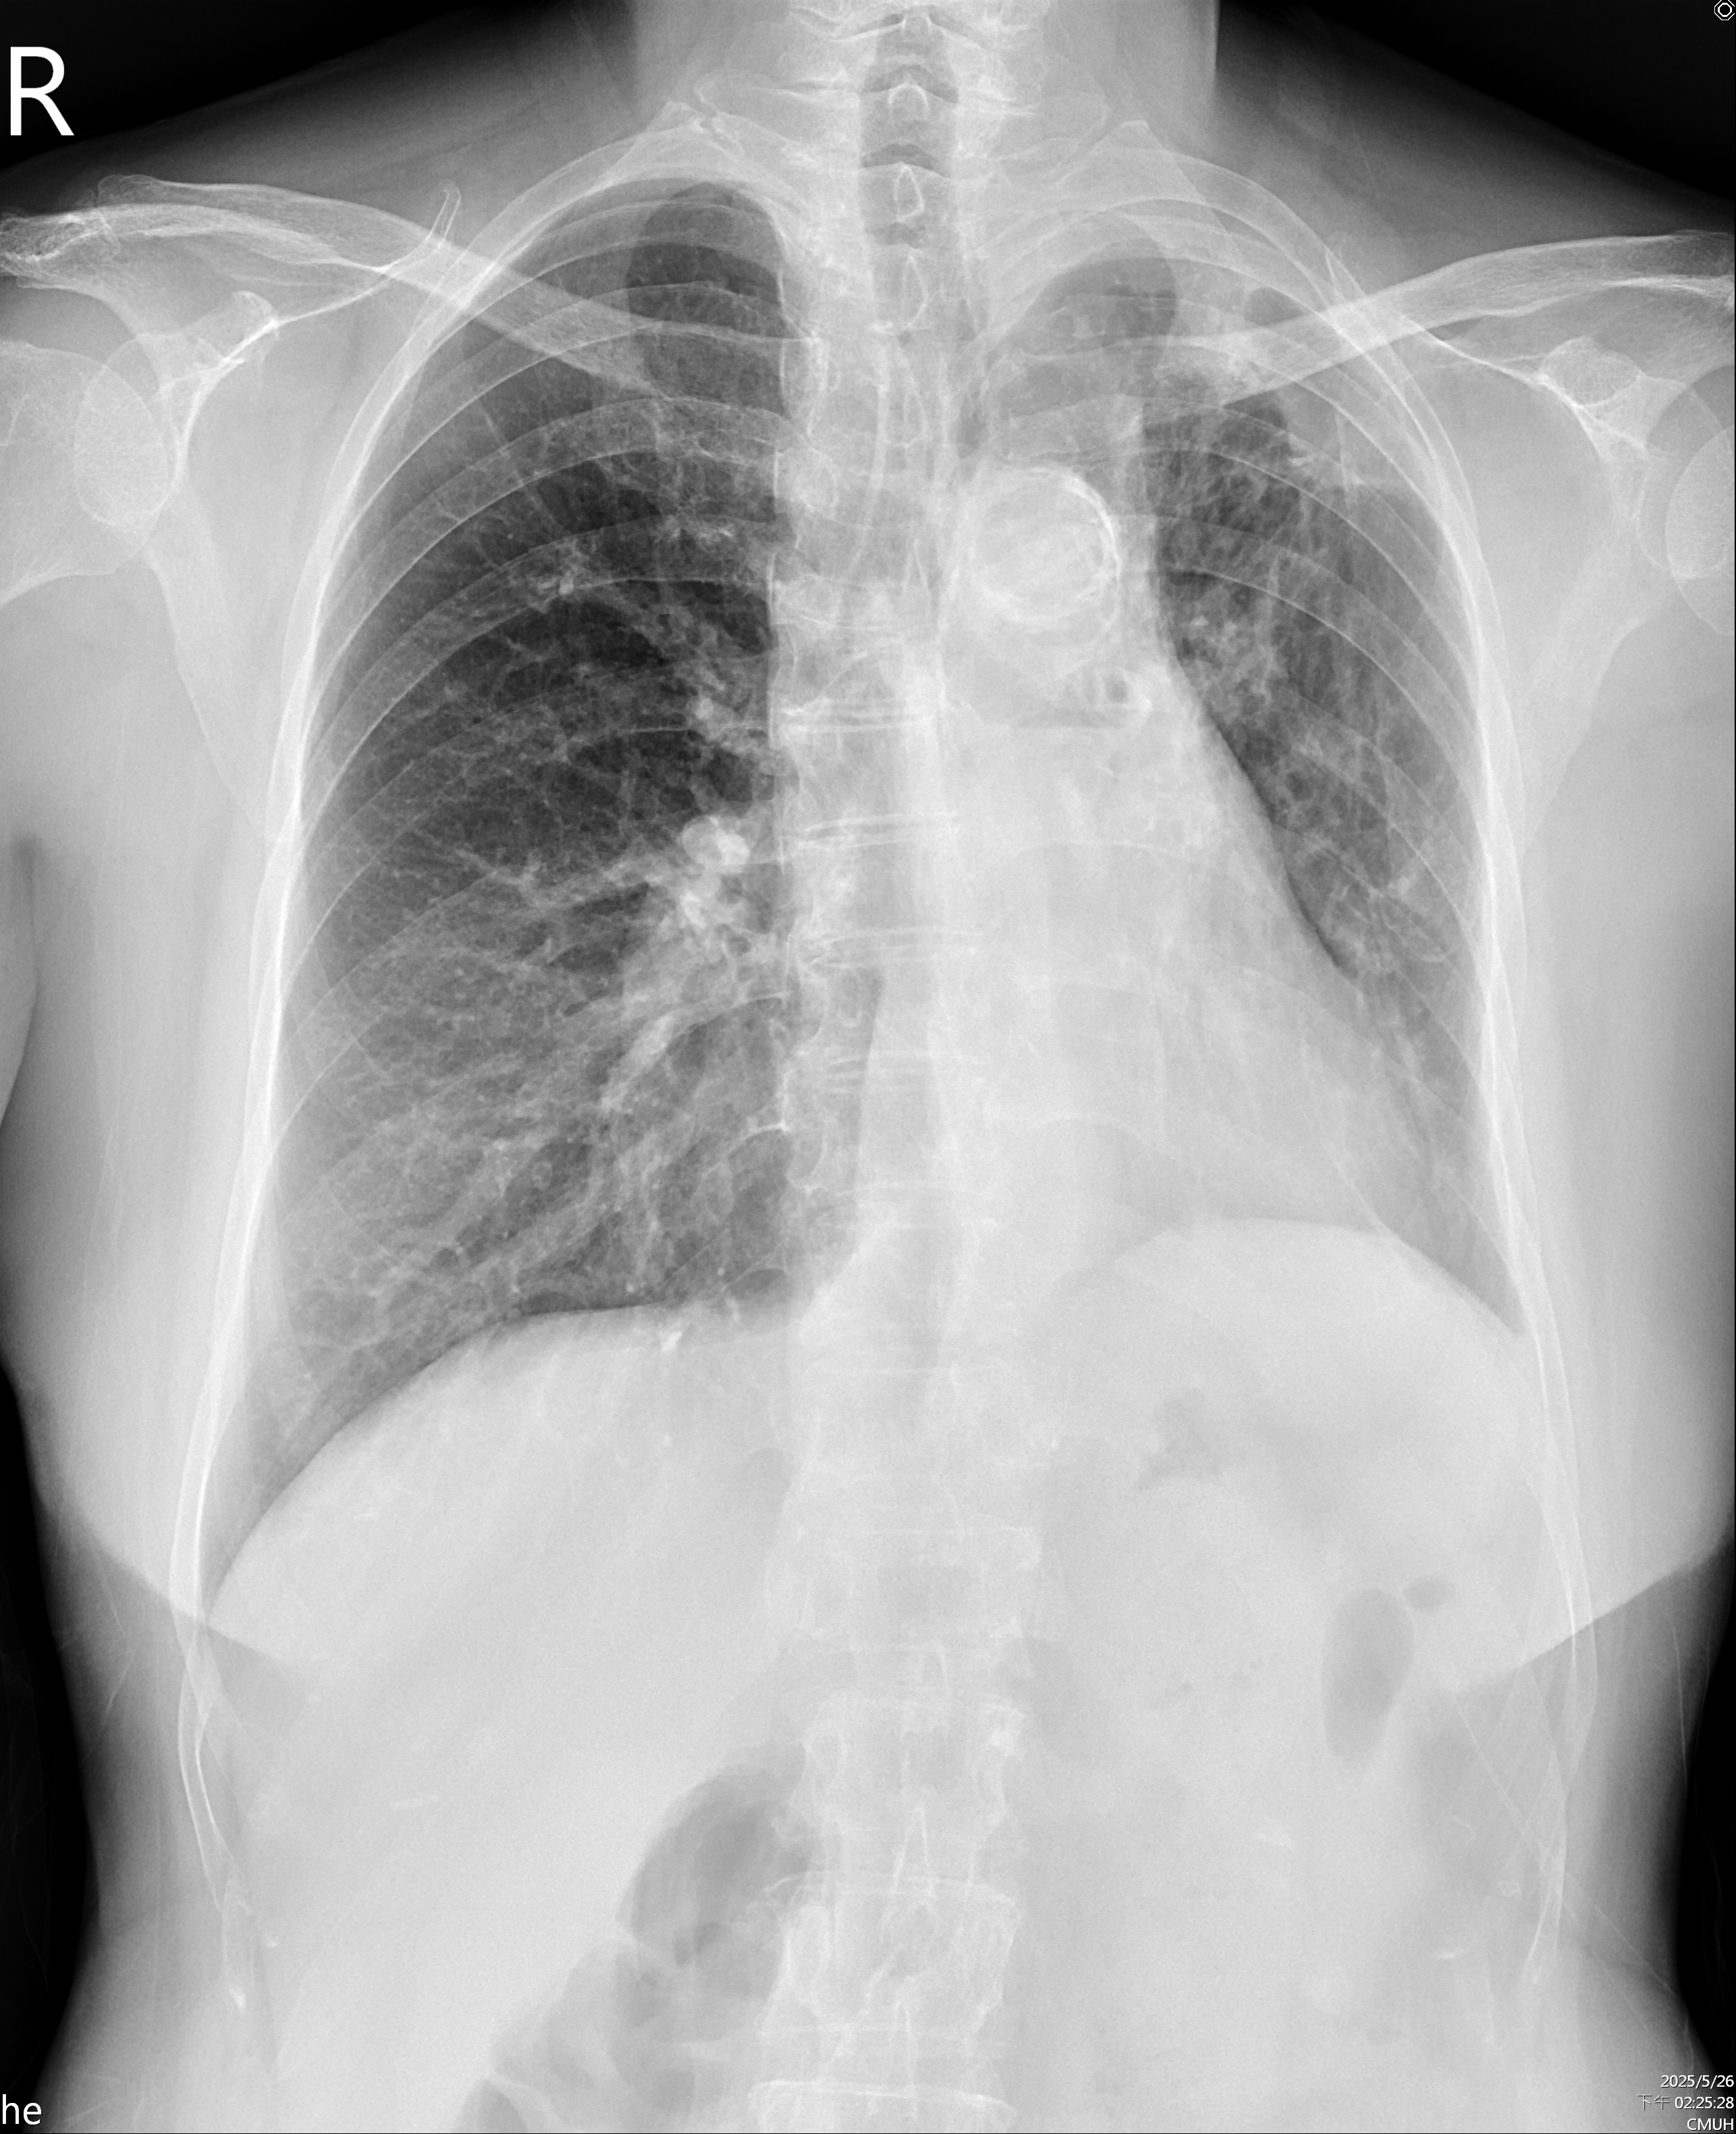

CXR: Tortuosity of the T-aorta without cardiomegaly, Calcification of aortic arch, bronchiectasis in both lower lungs.

Transthoracic Echocardiography: Preserved left ventricular ejection fraction, Normal right-sided size